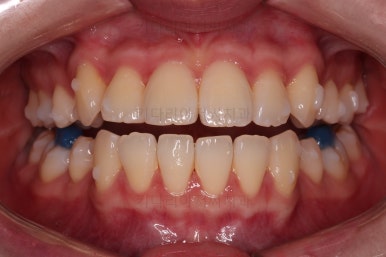

인비절라인을 착용한 모습인데요.

필요한 치아는 발치가 되어 있고요.

눈에는 잘 띄지 않지만 치아 색깔나는 재료로 어태치먼트라고 하는 부착물도 부착되어 있어요. 장치를 잘 잡아주는 손잡이와 같은 역할을 해줍니다.

어금니쪽을 잘 보시면 별표? 혹은 꽃모양 무늬가 그려진게 보이실텐데요.

이 그림이 있는게 인비절라인 정품입니다.

국내외 유사 투명교정 장치가 많이 나오고 있지만 아직은 기술력에서 인비절라인이 가장 앞서 있어서 저희 부산교정전문의 키다리아저씨치과에서는 투명교정은 인비절라인으로 현재 진행하고 있습니다.